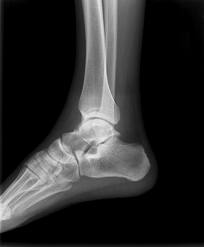

Gli esiti di fratture articolari che hanno coinvolto il malleolo tibiale o peroneale, fratture dell’estremo distale di tibia oppure un quadro di degenerazione cartilaginea possono portare alla formazione di calcificazioni articolari, corpi mobili oppure “osteofiti” che deformano l’articolazione rendendola non più congruente e quindi con un arco di movimento ridotto.

Gli accertamenti strumentali sono essenzialmente rappresentati da una radiografia standard in due proiezioni della caviglia, sufficiente a dimostrare la deformazione dei capi articolari, eventualmente accompagnata da una RM per meglio definire la situazione dei tessuti molli (capsula articolare, legamenti, cartilagine, etc.)